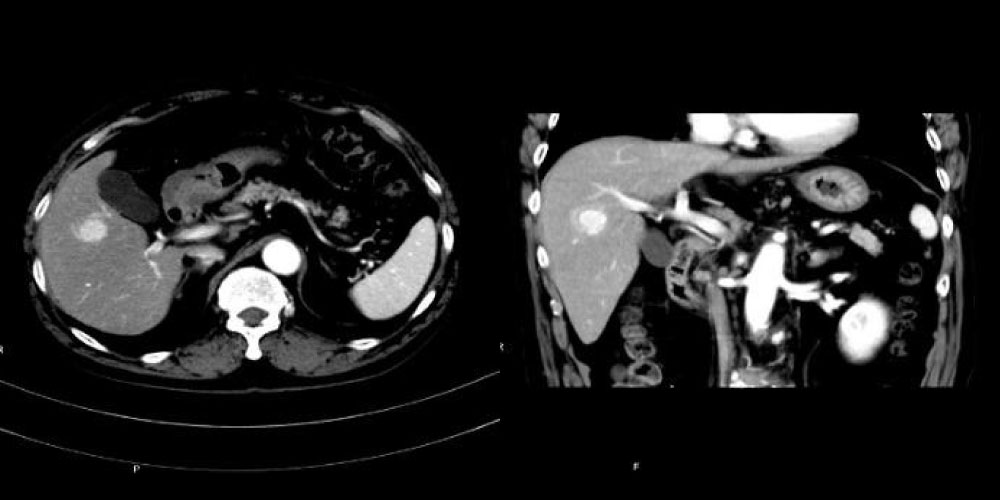

腹部領域

腹部CT検査は、臓器(肝臓、腎臓、膵臓など)や血管の状態を調べることが可能です。

急性腹症の原因や腫瘍性病変などの病気の性質を調べるため、造影剤を使用することもあります。